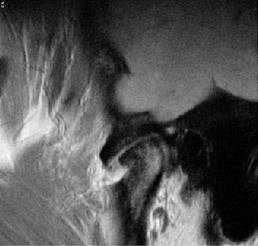

В настоящее время наиболее безопасным и косметичным является хирургическое вмешательство в ВНЧС с помощью артроскопа. Показанием для лечебно-диагностической атроскопии явились значительное ограничение открывания рта, наличие болей в области сустава, отсутствие эффекта от консервативного лечения. Лечебно-диагностическая артроскопия проведена 18 пациентам. У всех больных обнаружен процесс склерозирования - были видны множественные фиброзные спайки, фиксирующие суставной диск к поверхности головки нижней челюсти или височной кости. Спайки обнаружены как в нижнем, так и в верхнем отделах сустава, но больше и чаще в нижнем. Надо отметить, что фиброзные спайки не визуализировались при МРТ и УЗИ. С помощью гидравлического воздействия жидкости для промывания полостей сустава (0,9% раствор натрия хлорида) и специальных инструментов обнаруженные спайки разрушены и удалены (рис. 3). Рисунок 3. Лечебно-диагностическая артроскопия. а — фиброзные спайки (1) между головкой нижней челюсти (2) и суставным диском (3). Рисунок 3. Лечебно-диагностическая артроскопия. б — удаление спаек с помощью инструмента (кусачек).